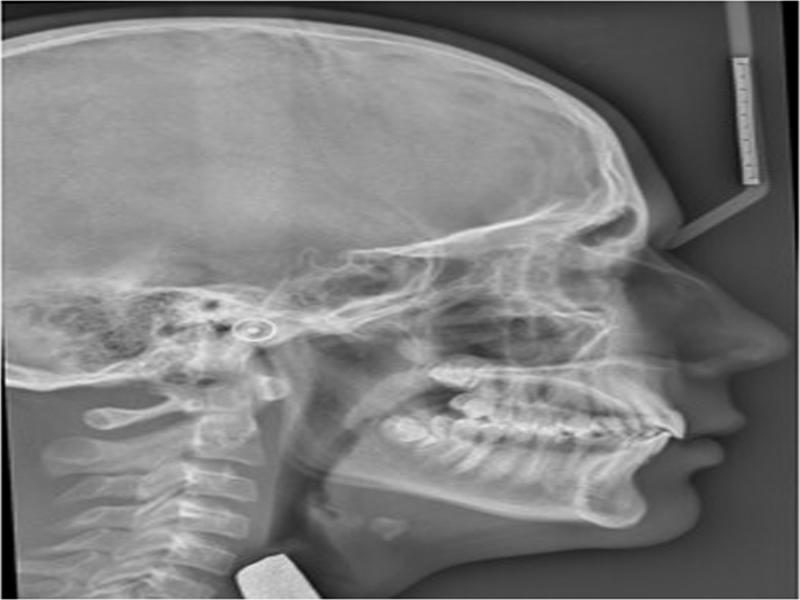

Figure 3.

Cephalometric summary

| Measurement | Std | Pre-Rx | Post-Rx | Change | |

|---|---|---|---|---|---|

| SKELETAL | |||||

| Maxilla | SNA | 82 | 88 | 88.3 | 0.3 |

| A Point Convexity | 3 | 2.9 | 2.5 | -0.4 | |

| NaVert - A point | 1 mm | 1.8 | 2.6 | 0.8 | |

| Mandible | SNB | 80 | 83.3 | 84 | 0.7 |

| Facial Angle | 87 | 88.9 | 92.2 | 3.3 | |

| NaVert - Po | -8 to -6 mm/-2 to 4 mm | -2.1 | 2.1 | 4.2 | |

| Basal Arch Relationship | ANB | 2 | 4.7 | 4.3 | -0.4 |

| WITS | F: 0 mm | 3.1 | 0 | -3.1 | |

| Vertical | Md Plane Angle | 26 | 20.9 | 18.7 | -2.2 |

| LFH Angle | 47 | 43.9 | 46.3 | 2.4 | |

| Md Arc | 26 | 37.1 | 39.8 | 2.7 | |

| Facial Axis Angle | 90 | 90.7 | 90.8 | 0.1 | |

| Jarabak ratio | 0.59.0.63 | 0.73 | 0.74 | 0.01 | |

| DENTAL | |||||

| Upper Incisors | UI to FH | 110° | 115.9 | 120.4 | 4.5 |

| UI to Pal Plane | 110° | 114.7 | 117.5 | 3.8 | |

| UI to Na Vert | 5 mm | 3.3 | 5 | 1.7 | |

| Lower Incisors | LI to Md Plane | 92.5° | 101.6 | 104.5 | 2.9 |

| LI to Apo | 22 | 28.2 | 31.7 | 3.5 | |

| LI to Apo | 1 | 2.7 | 4.5 | 1.8 | |

| Interincisal | UI to LI | 130 | 121.6 | 114.4 | -7.2 |

| SOFT TISSUE | L Lip - E Line | -2 | -2.4 | -1.1 | 1.3 |

| SnVert - U Lip | 1 mm | 2.2 | 3.3 | 1.1 | |

| SnVert - L Lip | -1 mm | -4.1 | 0.2 | 4.3 | |

| SnVert - Po' | -3 mm | -8.4 | -3.8 | 4.6 | |